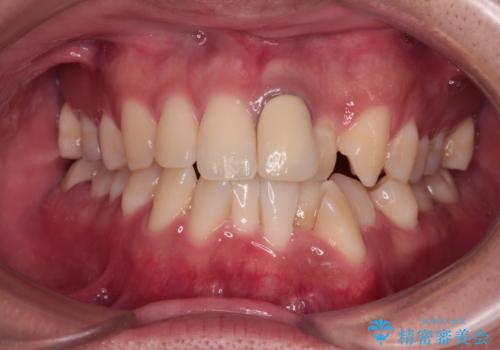

- 前歯のデコボコや八重歯を気にして来院された患者様です。

他院でワイヤー矯正を行うつもりでいらっしゃったそうですが、通院が難しくなったとのことで当院での治療を希望されて来院されました。

上下ともに歯列幅が狭く、その影響でデコボコになっていたため、ワイヤー装置を用いて歯列を側方に拡大しながら、デコボコを解消していくこととしました。